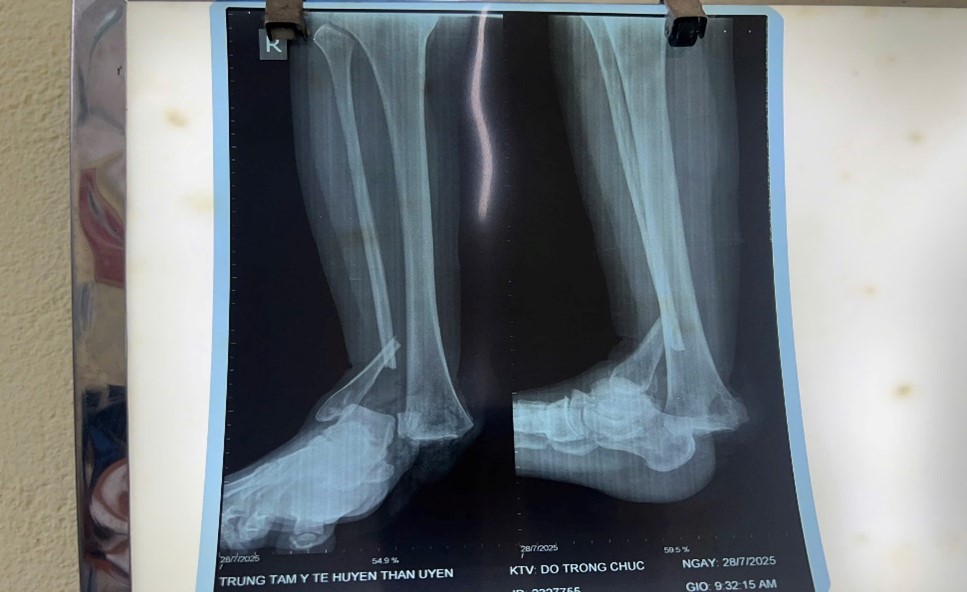

Hình ảnh chấn thương của Bệnh nhân lúc chưa phẫu thuật

Vào lúc 09 giờ 57 phút ngày 28/7/2025, Trung tâm Y tế Than Uyên tiếp nhận bệnh nhân nữ, 41 tuổi, trú tại xã Chiềng Bằng, tỉnh Sơn La, vào viện trong tình trạng cổ chân phải bị chấn thương nặng, biến dạng, chảy máu nhiều do ngã xe máy. Sau khi thăm khám, hội chẩn, bệnh nhân được chẩn đoán gãy hở 1/3 dưới xương mác, gãy mắt cá trong, bật khớp cổ chân phải, cần được phẫu thuật cấp cứu.